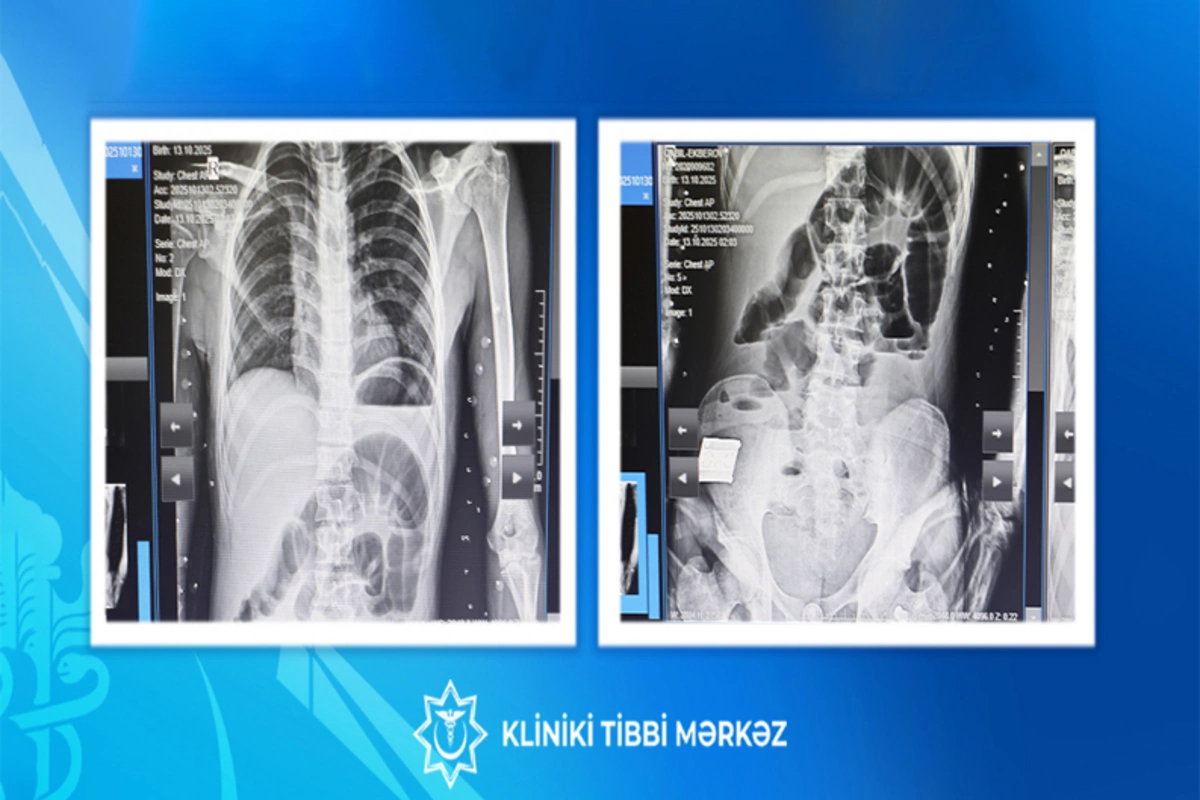

17 yaşlı yeniyetmə taxta udaraq qarın nahiyəsində kəskin ağrı, ürəkbulanma, təkrarlanan qusma və hipertermiya şikayətləri ilə Kliniki Tibbi Mərkəzin (KTM) Təcili və Təxirəsalınmaz Tibbi Yardım şöbəsinə gətirilib.

Bildirilib ki, müayinələr nəticəsində xəstəyə peritonit diaqnozu qoyulub və əməliyyatönü hazırlıqdan sonra təxirəsalınmaz cərrahi müdaxilə aparılıb. Nazik bağırsaq seqmentinin rezeksiyası, yoğun bağırsağın defektinin tikilməsi əməliyyatı icra olunub.

Əməliyyat zamanı nazik bağırsaqda, iliosekal küncdən 70–80 sm məsafədə, iki yerdə deşici (perforativ) zədələnmə müəyyən olunub. Bu perforasiyalara səbəb bağırsaq mənfəzində yerləşən iti və sərt yad cisim taxta parçası olub. Bundan əlavə, yoğun bağırsaqda da perforativ dəlik və bütün nazik bağırsaq boyunca mənfəz daxilində müxtəlif ölçülü, iti uclu, sərt yad cisimlər aşkarlanıb.

Uğurlu cərrahi müdaxilə və 8 günlük stasionar müalicə nəticəsində xəstənin vəziyyəti kafi qiymətləndirilib və o, ambulator müalicə üçün evə buraxılıb.